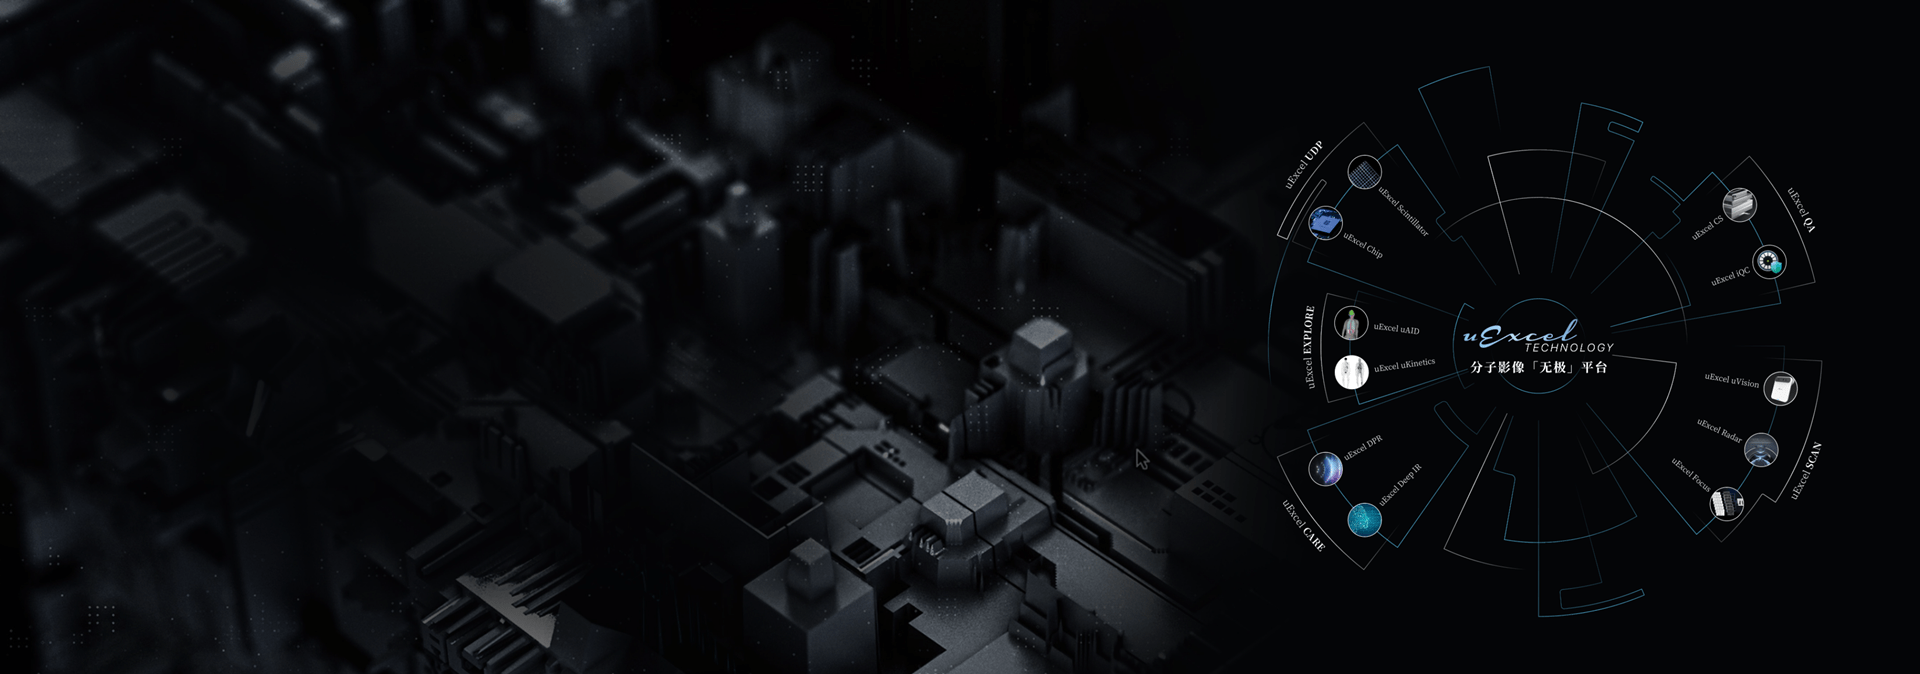

数智赋能 · 共筑生态

uMI Vista Pro基于uExcel Technology技术平台开发,对探测器硬件、图像重建、科研应用、设备质控管理进行全面赋能革新,致力于为临床诊断和前瞻科研探索提供更精准高效的影像手段。

uExcel Technology

全面赋能

uExcel Technology 以源头级创 「 芯 」 与 「 无极 」 探测器为牵引,集结精密晶体制造工艺、智能传感器、AI 重建引擎等核心技术,赋能新一代全数字化PET-CT系统 uMI Vista Pro,全面革新整机设计,开启精准诊疗新时代。